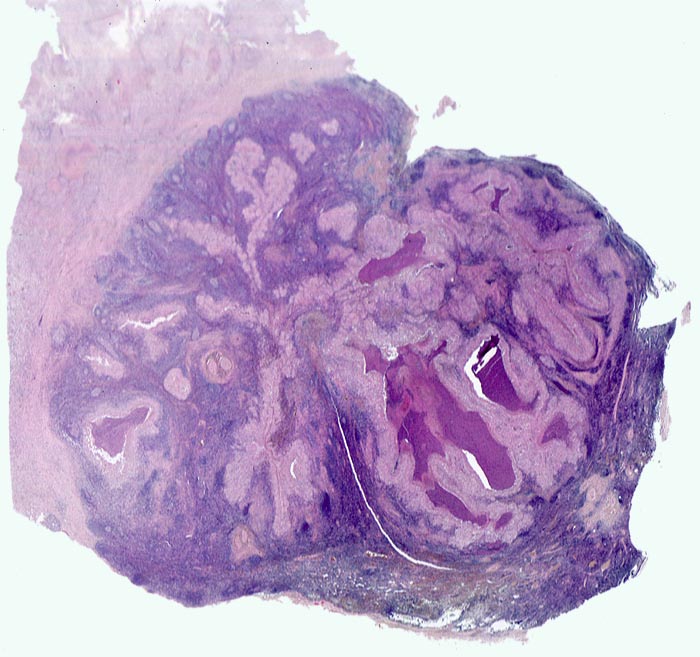

retikulozytär-abszedierende Lymphadenitis bei Katzenkratzkrankheit

Lymphknoten, Axilla

Links im Bild die stark fibrosierte Lymphknotenkapsel. Das Parenchym wird durchsetzt von girlandenförmigen Arealen mit zentraler Abszessbildung umgeben von einem hellen Saum aus Epitheloidzellen.

Druckschmerzhafte Lymphknotenvergrösserung in der rechten Axilla 2 Wochen nachdem der Patient von seiner Katze an der rechten Hand gekratzt wurde.